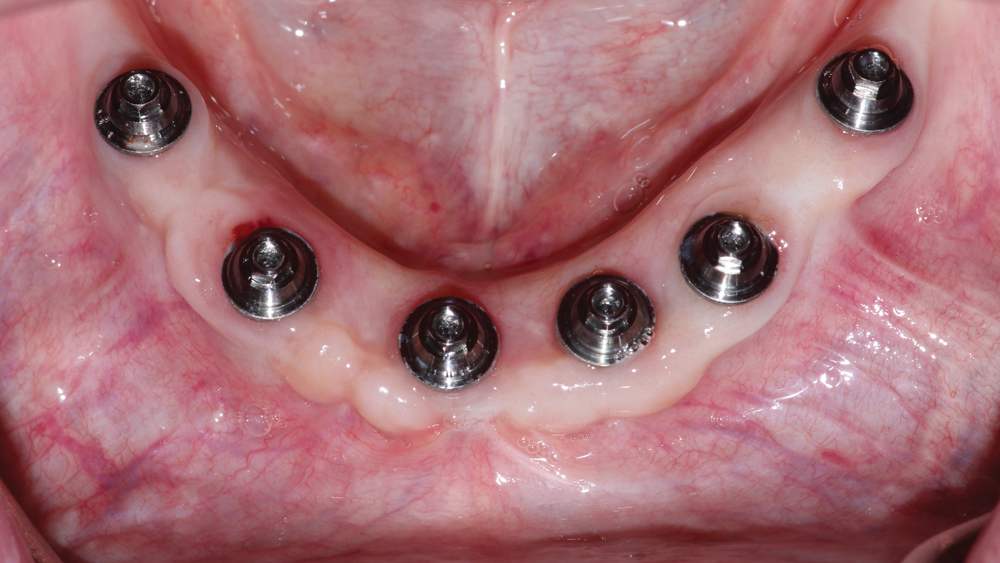

This patient was unhappy with the esthetics of her existing upper denture as well as the discomfort and instability caused by her loose-fitting mandibular partial denture. Although her concerns with the maxillary denture could be addressed with a new, more esthetic appliance, she preferred implant treatment for her mandible, where a fixed solution was needed to adequately restore function, stability and comfort.

Treatment plan:

The patient’s remaining mandibular teeth were extracted followed by immediate implant placement and delivery of a fixed provisional appliance. After integration of the implants, the prosthetic designs for the new upper denture and lower implant restoration were determined in tandem. Ultimately, the dual-arch restorations addressed the functional and esthetic challenges of the case while staying within the financial means of the patient, demonstrating the benefits of a flexible, multifaceted approach to restorative dentistry.